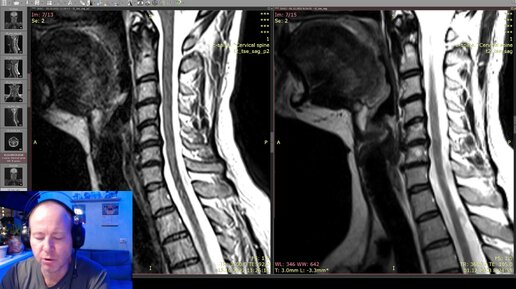

Неудачная мануальная терапия привела к воспалению

Мануальная терапия